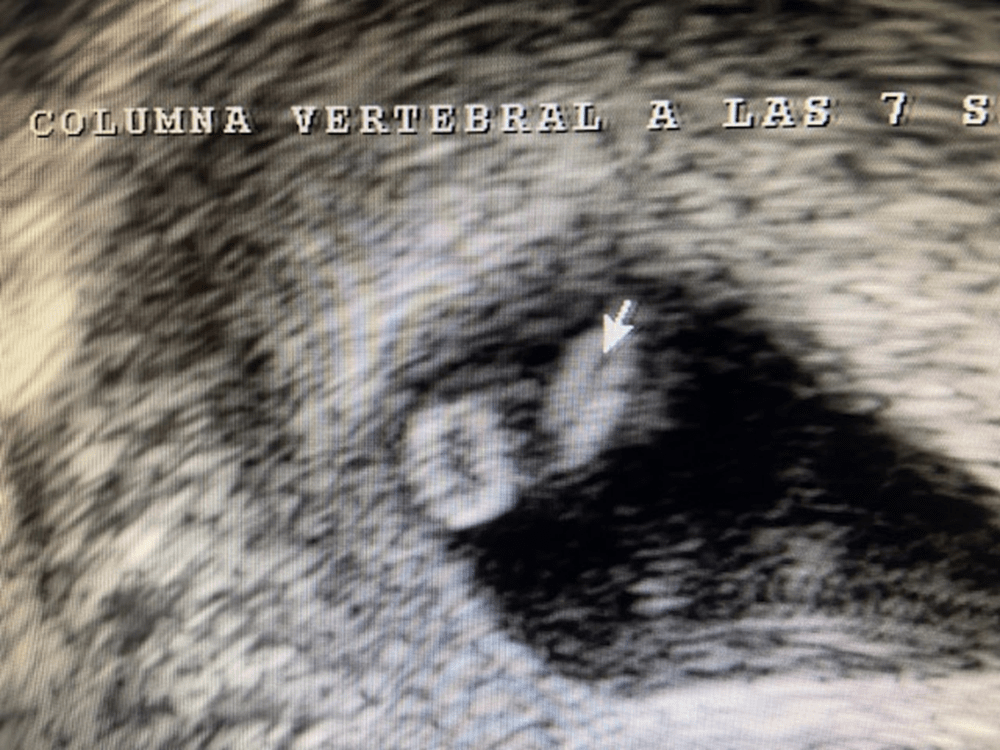

Para que toméis conciencia de lo importante que es tomar ácido fólico desde 2 a 3 meses antes de que se produzca el embarazo, observar, en la siguiente fotografía, como en un embrión de 7 semanas ya podemos visualizar su tubo neural. Es esa raya negra que parece dividirlo en dos. El tubo neural empieza a formarse a la 3ª semana de gestación y se acaba cerrando definitivamente al completar la 8ª.

Clínica Ginecológica Dr. Francisco Valdivieso.